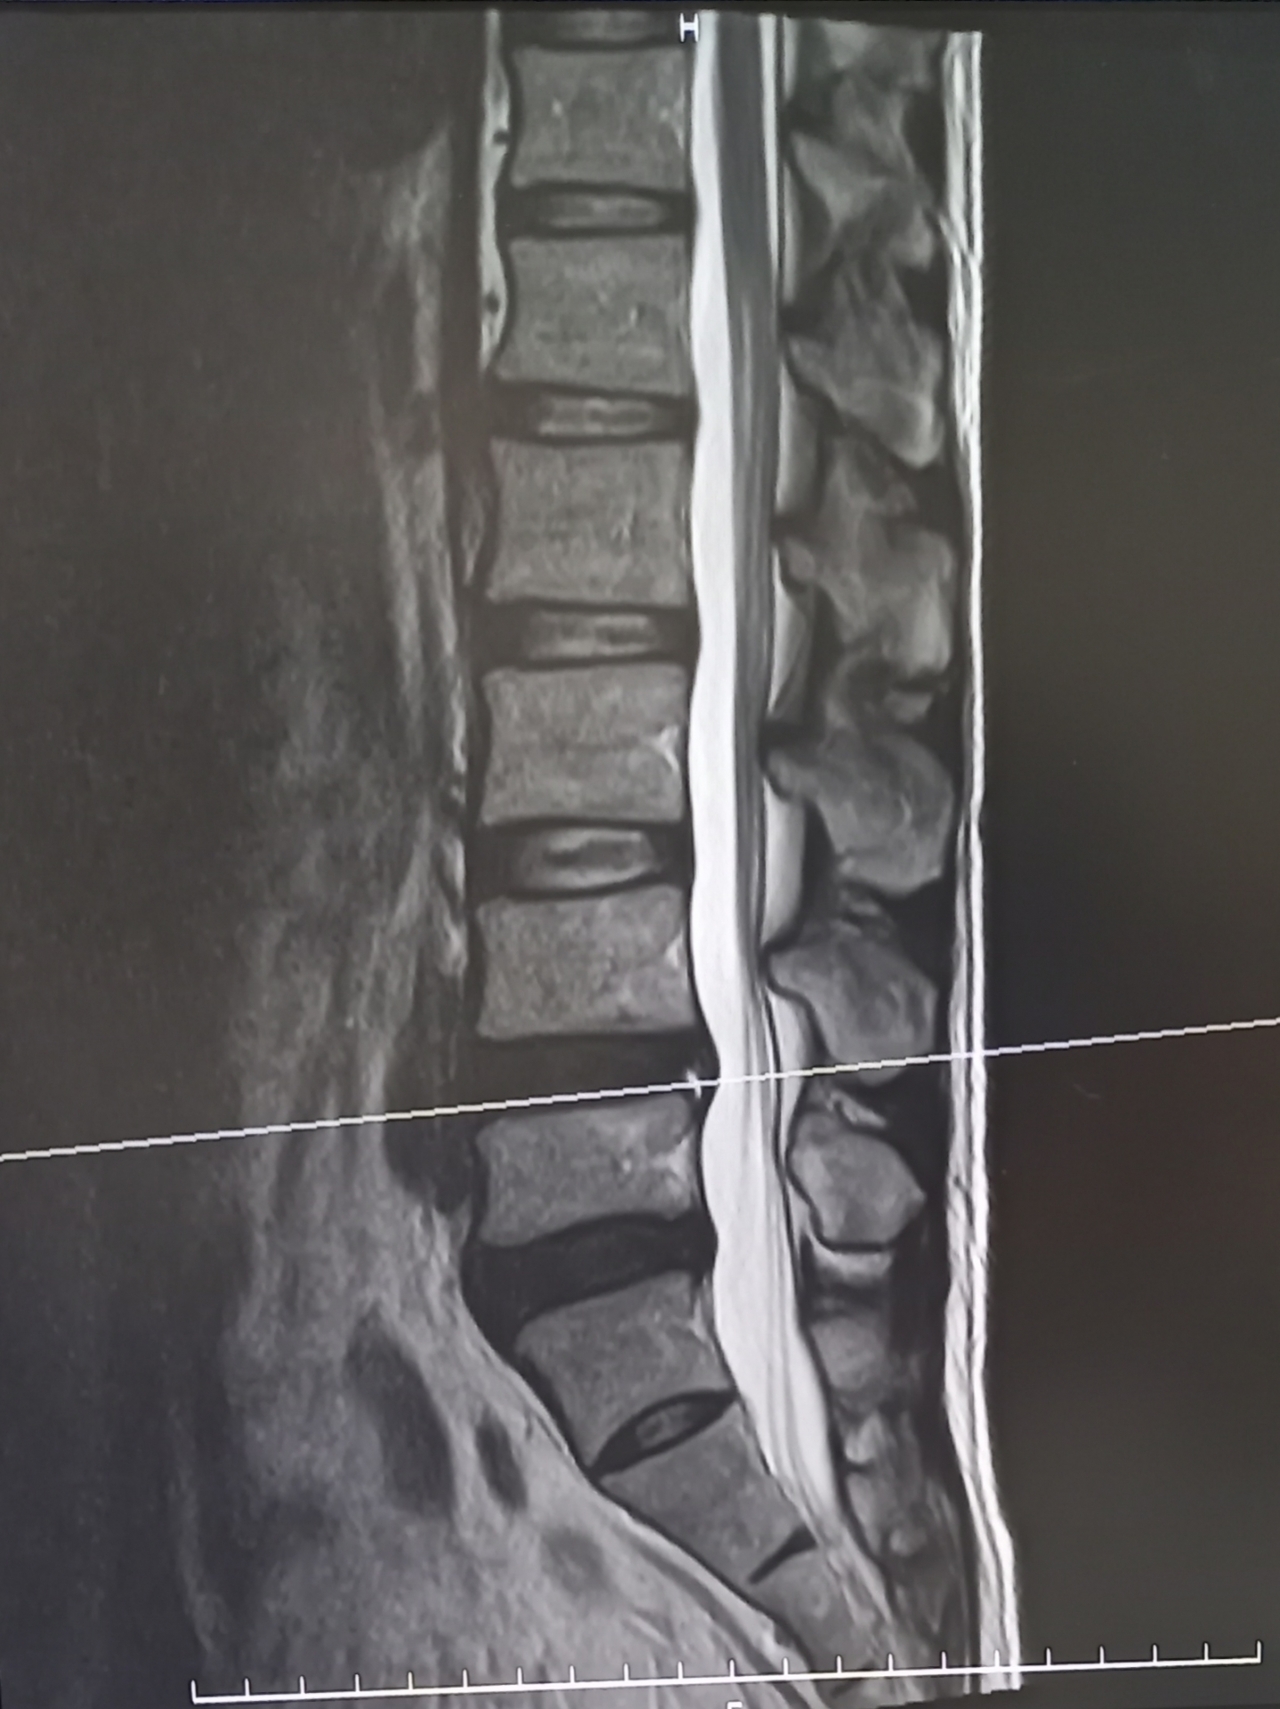

画像検査は「原因を探す」より「状態を確認する」ためのツール

画像検査の役目は骨や椎間板、神経の状態がどのようになっているかを確認することです。

• MRI=椎間板や神経を確認

しかし、画像の異常と痛みは必ずしも一致しません。